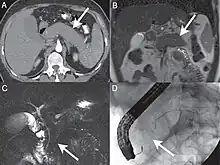

| A. Axial CT image in the pancreatic parenchymal phase shows the typical enlarged, poorly enhancing gland. B. Coronal T2 Weighted MR image demonstrates low signal intensity in the pancreas due to the diffuse fibrosis in the gland. C. Coronal MRCP image depicts a diffusely irregular pancreatic duct with stenosis distally in the pancreatic head. D. ERCP confirms the MR findings including the ductal stenosis. | |

Computed tomography (CT) findings in AIP include a diffusely enlarged hypodense pancreas or a focal mass that may be mistaken for a pancreatic malignancy.[8] A low-density, capsule-like rim on CT (possibly corresponding to an inflammatory process involving peripancreatic tissues) is thought to be an additional characteristic feature (thus the mnemonic: sausage-shaped). Magnetic resonance imaging (MRI) reveals a diffusely decreased signal intensity and delayed enhancement on dynamic scanning. The characteristic ERCP finding is segmental or diffuse irregular narrowing of the main pancreatic duct, usually accompanied by an extrinsic-appearing stricture of the distal bile duct. Changes in the extrapancreatic bile duct similar to those of primary sclerosing cholangitis (PSC) have been reported.